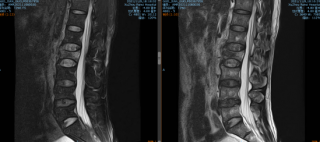

科室选派医生到北京、上海、苏州等重点医院进修,开展各类脊柱疾病颈腰腿疼痛疾病的诊疗和腰椎管狭窄、腰椎间盘突出症、腰椎间盘源性疼痛、脊柱侧弯、脊柱骨折等脊柱手术,积累了丰富的临床经验。

• 1、微创经椎间孔椎体融合术(MIS-TLIF)

• 2、颈椎前路椎间盘摘除融合内固定术(ACDF)

• 3、显微镜下髓核摘除术

• 4、微创脊柱内镜下髓核摘除术

• 5、天玑骨科机器人辅助下全脊柱微创手术

擅长:腰椎滑脱后路复位经皮椎弓根螺钉植入,微创经椎间孔椎体间融合术(MIS-TLIF);腰椎间盘突出微创脊柱内镜下髓核摘除术;显微镜辅助下颈椎间盘摘除椎间融合内固定术;颈前路椎间盘摘除+椎间融合+内固定术;颈椎后路椎管扩大成形术,颈椎后路减压侧块螺钉固定术;天玑机器人辅助下脊柱骨折及退变性疾病微创手术等。

擅长:脊柱内镜下及显微镜下颈腰椎手术,显微腰椎间盘髓核切除术,骨质疏松性脊柱骨折微创治疗(椎体成形术),微创经椎间孔椎体间融合内固定术(MIS-TLIF),四肢骨关节创伤手术。

擅长:脊柱骨折手术,颈椎病前后路手术,腰椎间盘突出、椎管狭窄及滑脱手术,退变性脊柱侧弯手术,复杂的四肢和关节骨折手术,腰椎间盘突出症孔镜手术,天玑机器人辅助下脊柱骨折及退变性疾病微创手术等。